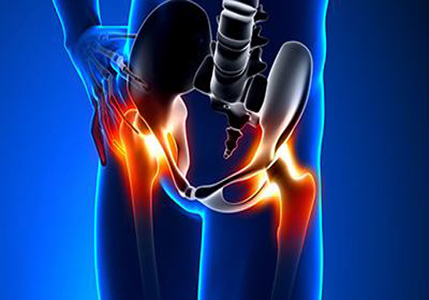

股骨头坏死患者肌肉萎缩主要是因为大腿的血液供应减少造成的。股骨头坏死的发生虽然原因各个有不同,但是发病肌机理都是导致股骨头周围血液循环障碍。

血液循环障碍不但会造成股骨头坏死,同时还会造成骨动脉都下肢广泛组织的血液供应减少,下肢肌肉长时间营养不良,就会造成下肢肌肉萎缩。第二种原因是,患肢大腿由于疼痛不经常走路负重,肌肉长时间得不到有效的锻炼肌肉不再发育,肌肉逐渐萎缩变小,造成的废用性肌肉萎缩。

对于股骨头坏死所导致的肌肉萎缩,其实并非都能恢复。之所以同样是肌肉萎缩,有的人能恢复,有的人不能恢复的问题,主要原因出在股骨头坏死的程度上。中早期股骨头坏死股骨头外形多大的破坏,修复后股骨头外形基本正常,不影响走路功能,将来病人走路距离不受影响,负重也不受影响。同时早期股骨头坏死血液循环破坏也不严重,通过治疗可以恢复,下肢血液供应不受影响,股动脉完全能够满足下肢用血液的需要,这样通过锻炼下肢肌肉萎缩可以恢复。

中晚期股骨头坏死就不一样了,股骨头塌陷严重,股骨头外形无法恢复,髋关节功能无法恢复,行走距离不能达到正常。股骨头周围血管部分消失终身不能恢复,下肢血运循环不能满足肌肉发育的需要,肌肉在缺乏血液营养的条件下不可能正常发育,这样一部分股骨头坏死患者的下肢肌肉萎缩就不可能恢复。